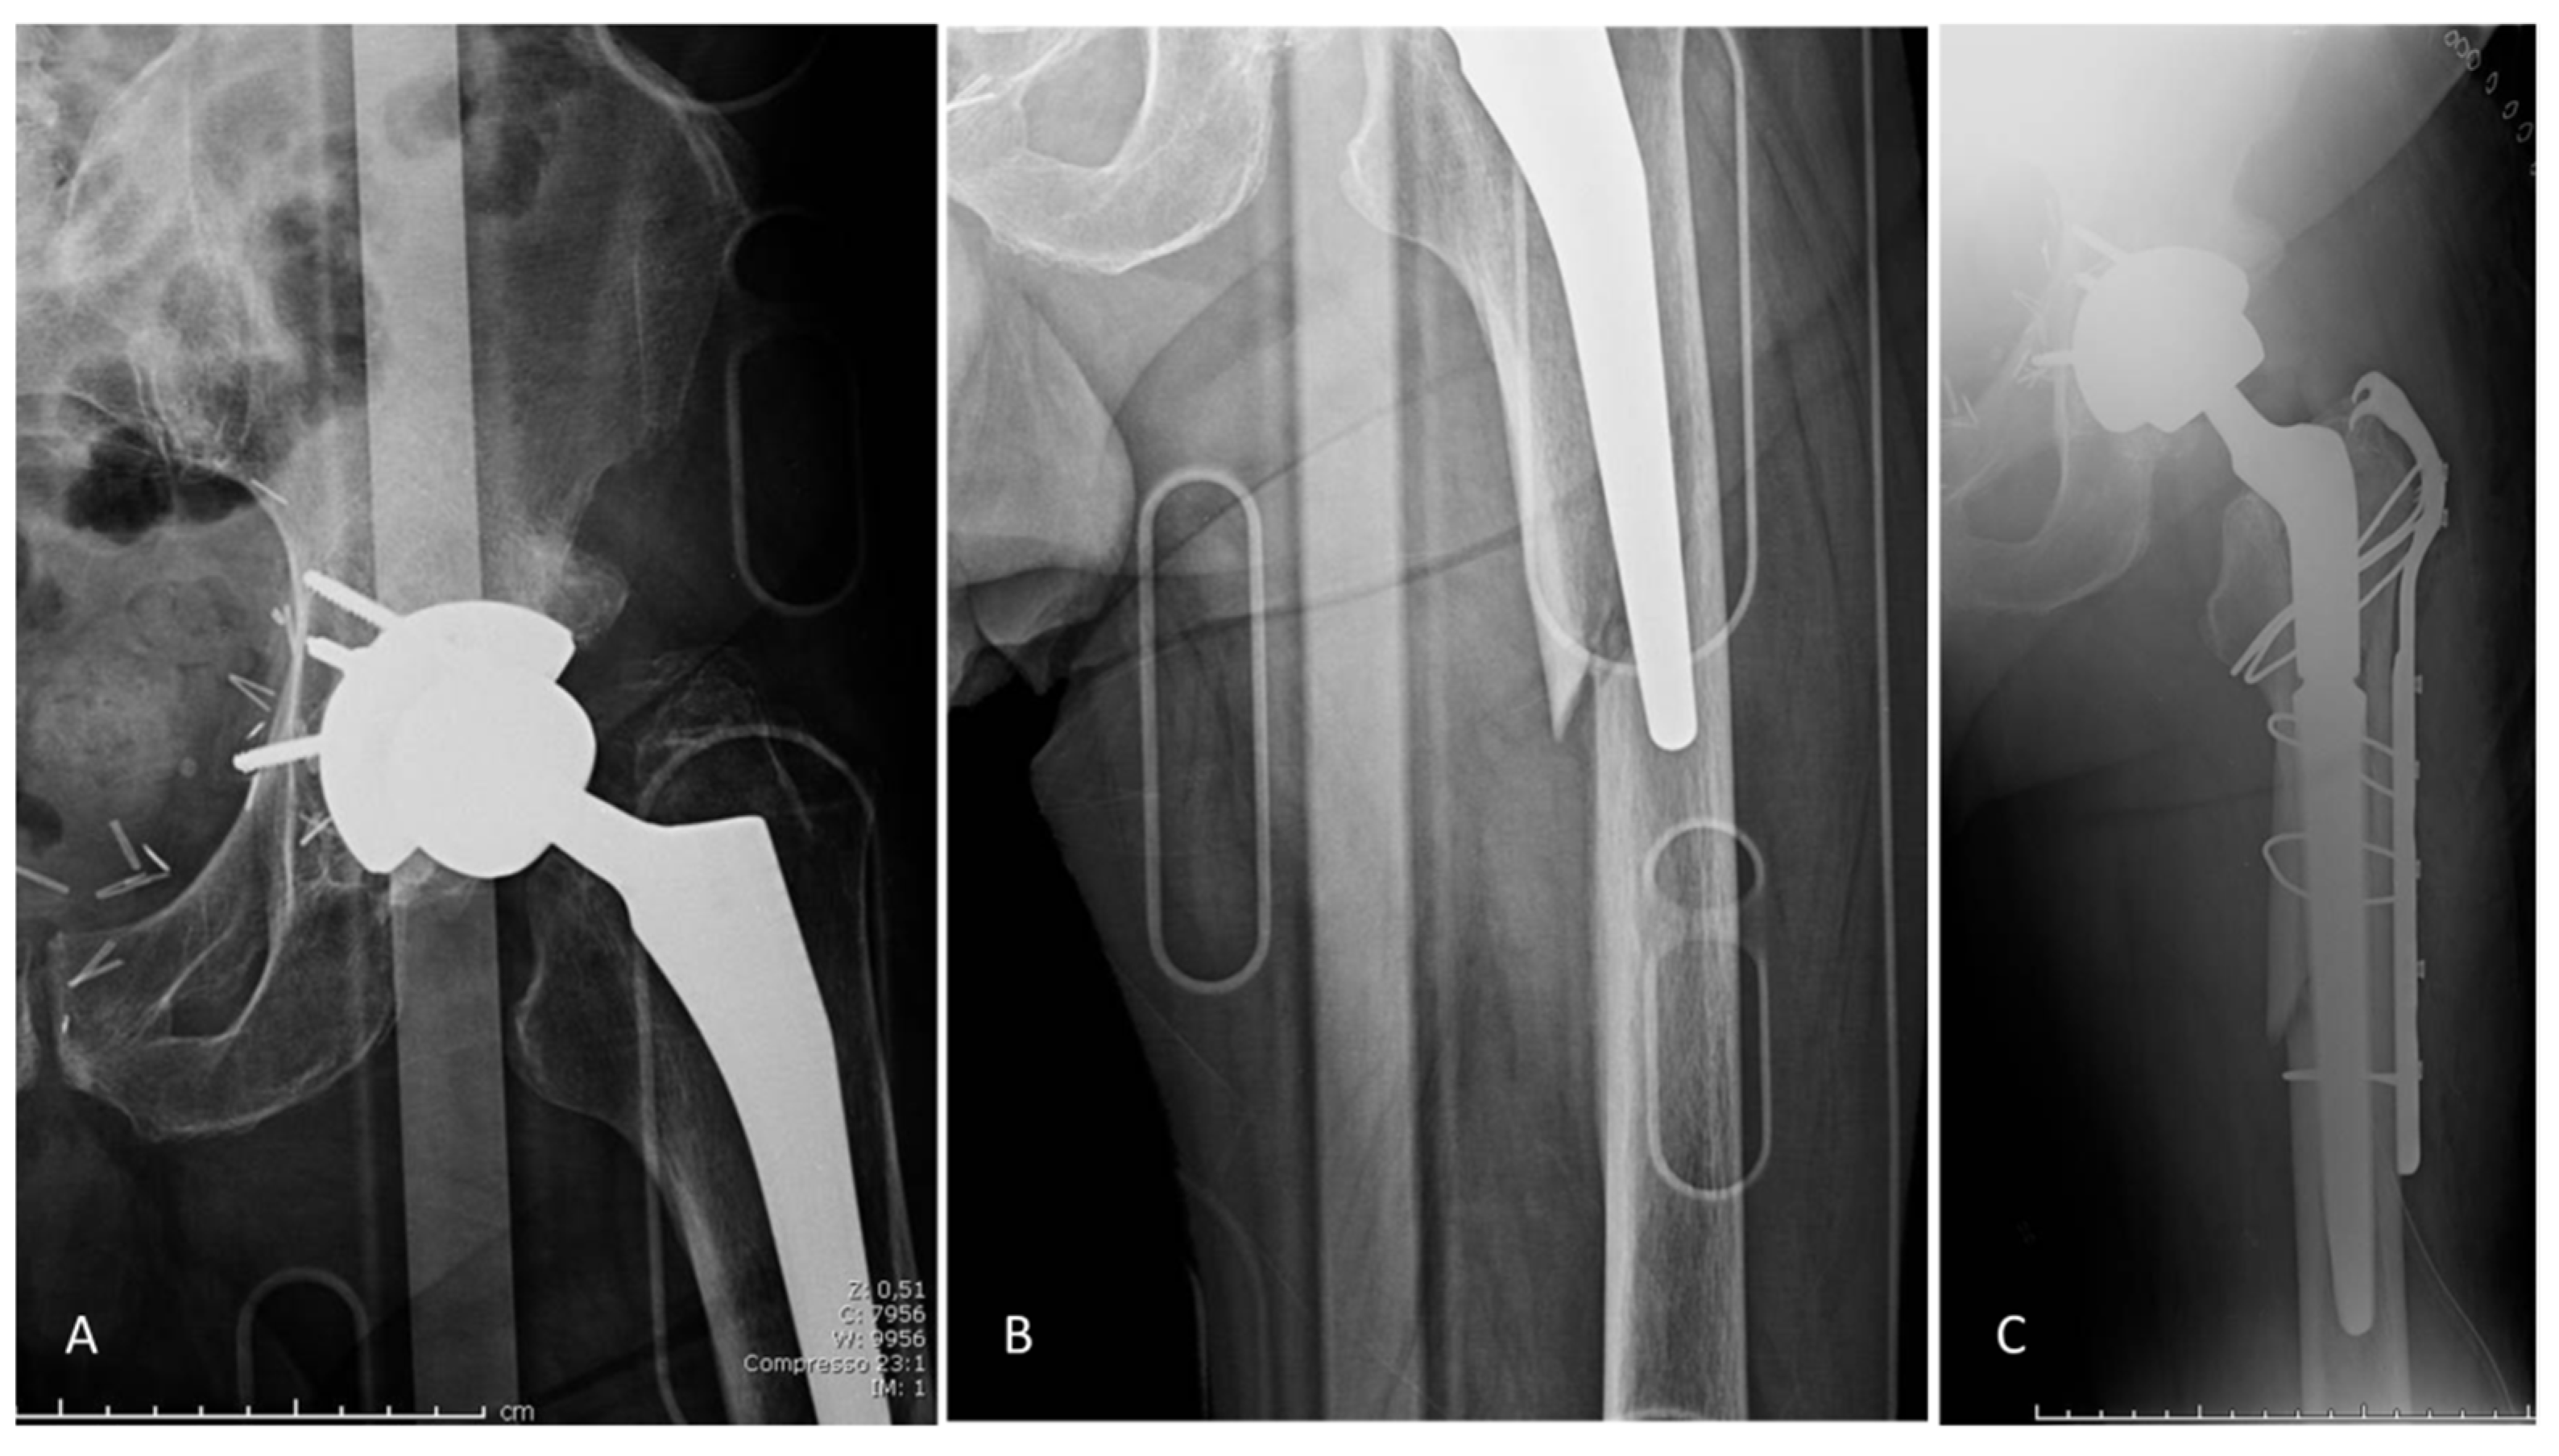

3.1. Complications

3.2. Implant Survival